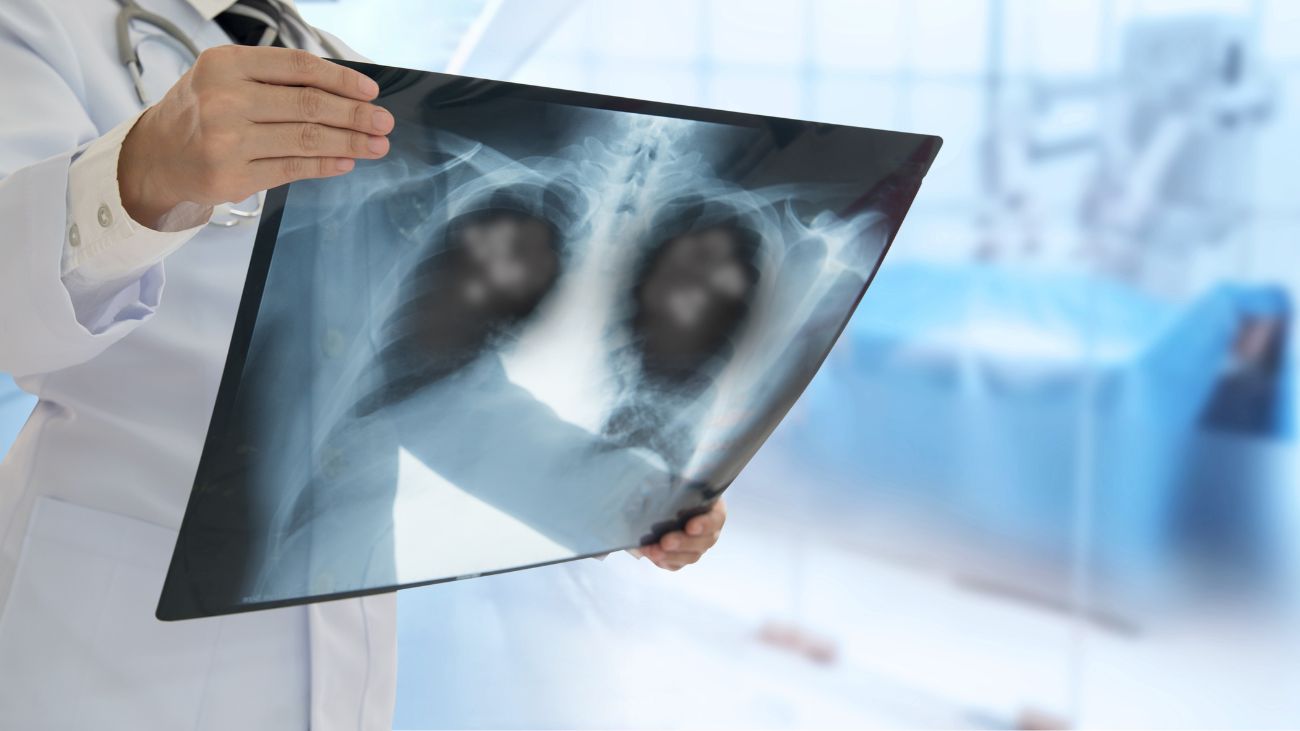

En Chile se está experimentando uno de los brotes de neumonía más significativos en las últimas décadas, ocasionado por una bacteria conocida como mycoplasma, que ha generado un aumento alarmante en los casos registrados.

En el último año, Chile ha visto un incremento sin precedentes de más de mil seiscientos casos relacionados con una bacteria denominada mycoplasma. Esta bacteria es conocida por causar diversas enfermedades respiratorias incluyendo neumonía y bronquitis. Los expertos en salud están alarmados por la magnitud del brote, considerando que es el más grande en dos décadas.

A diferencia de las neumonías virales, la neumonía causada por mycoplasma es de origen bacteriano. Esto ha llevado a un equipo multidisciplinario de especialistas en salud, incluyendo pediatras y broncopulmonares, a exigir al Ministerio de Salud claridad en las causas subyacentes detrás del incremento de casos.

La Dra. Gema Pérez, una destacada broncopulmonar, ha señalado que el mycoplasma «es capaz de producir tos excesiva o ataques de tos,» además de otros síntomas respiratorios tradicionales como la bronquitis y la propia neumonía.